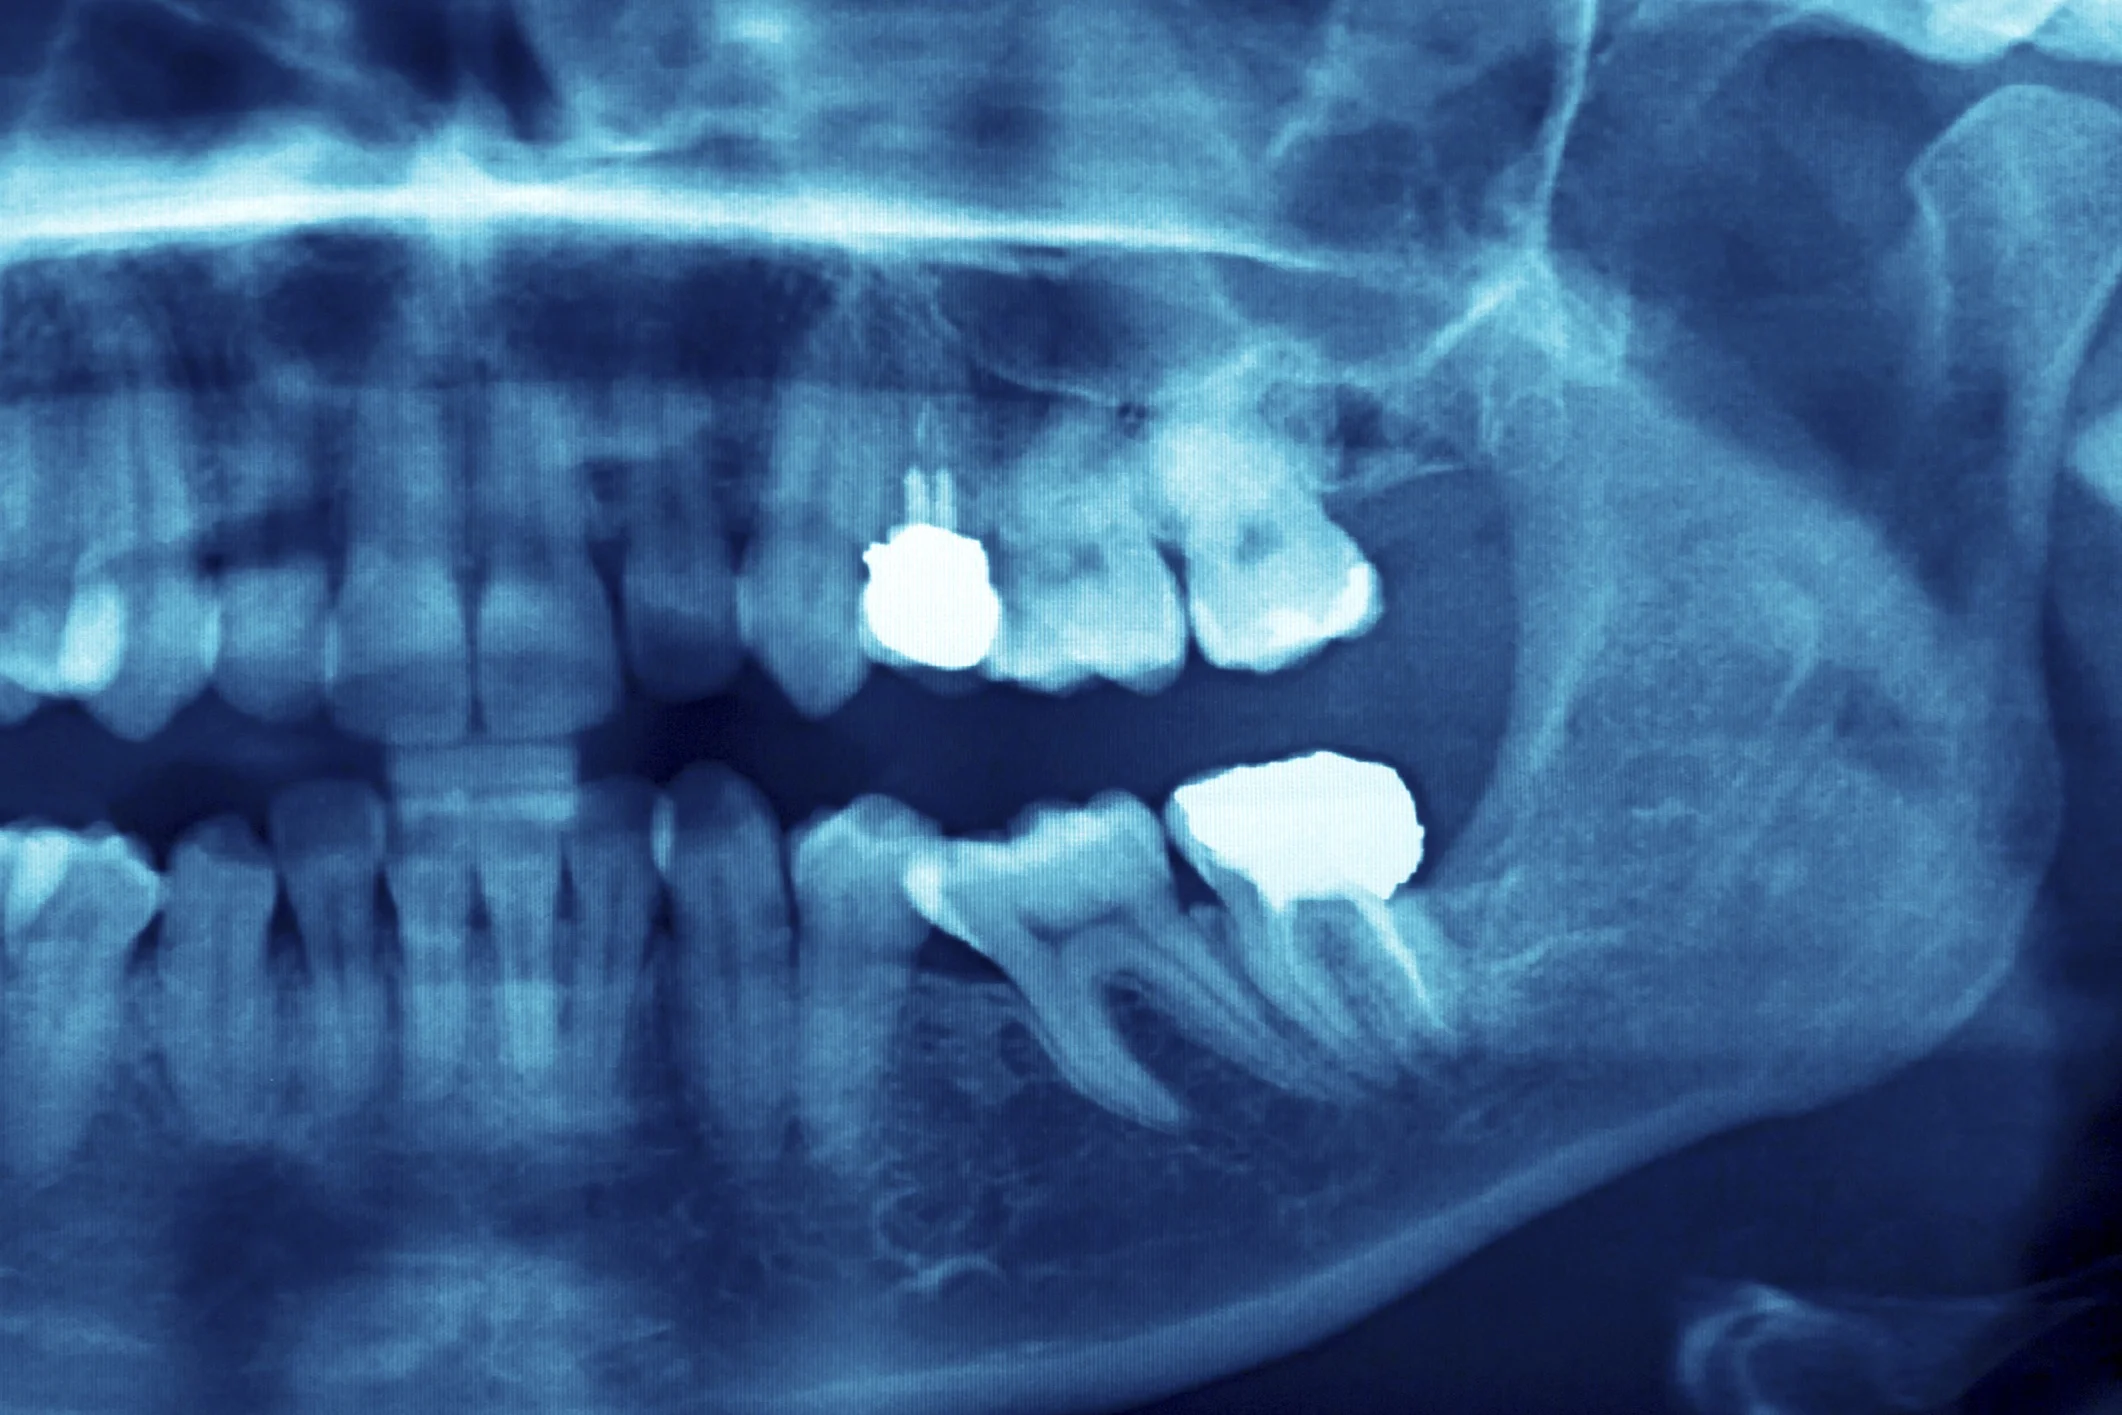

/Dental implants are the strongest, most durable solution for missing teeth. Made of high-quality materials, implants are designed to last for many years, so long as you take care of them. In this blog post, the team at Town Center Dentistry shares a few tips on how to make your dental implants last for years to come.